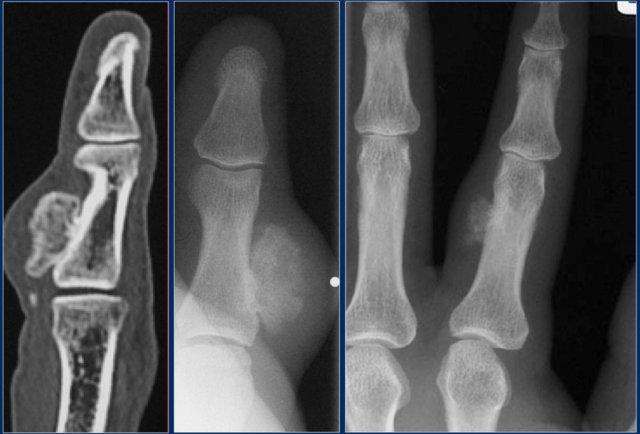

Subungual exostoses

Xương thừa dưới móng là những phần lồi xương xuất phát từ bề mặt lưng của đốt ngón xa, thường gặp nhất ở ngón cái.

Những tổn thương này không phải là u xương sụn, mà bao gồm sụn phản ứng dị sản.

The radiographic appearance and location are typical.

Nora’s lesion

Đây là hai bệnh nhân mắc tăng sinh xương sụn cạnh màng xương kỳ lạ (BPOP), còn được gọi là tổn thương Nora.

Quá trình phản ứng lành tính này thường gặp nhất ở vùng tiếp giáp với vỏ xương của các đốt ngón tay hoặc ngón chân (75%).

Vỏ xương và khoang tủy xương không bị tổn thương.

Sự phát triển nhanh chóng của khối vôi hóa không phải là hiếm gặp.